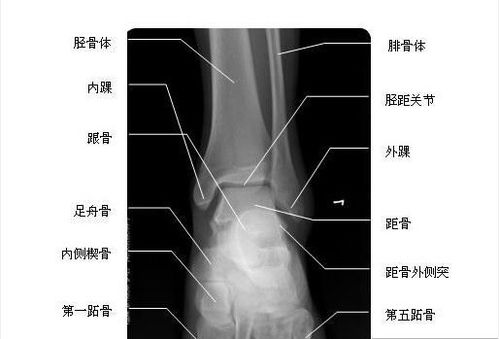

踝关节正位-x线-解剖图片

踝关节正位片解剖图

踝关节x线解剖图